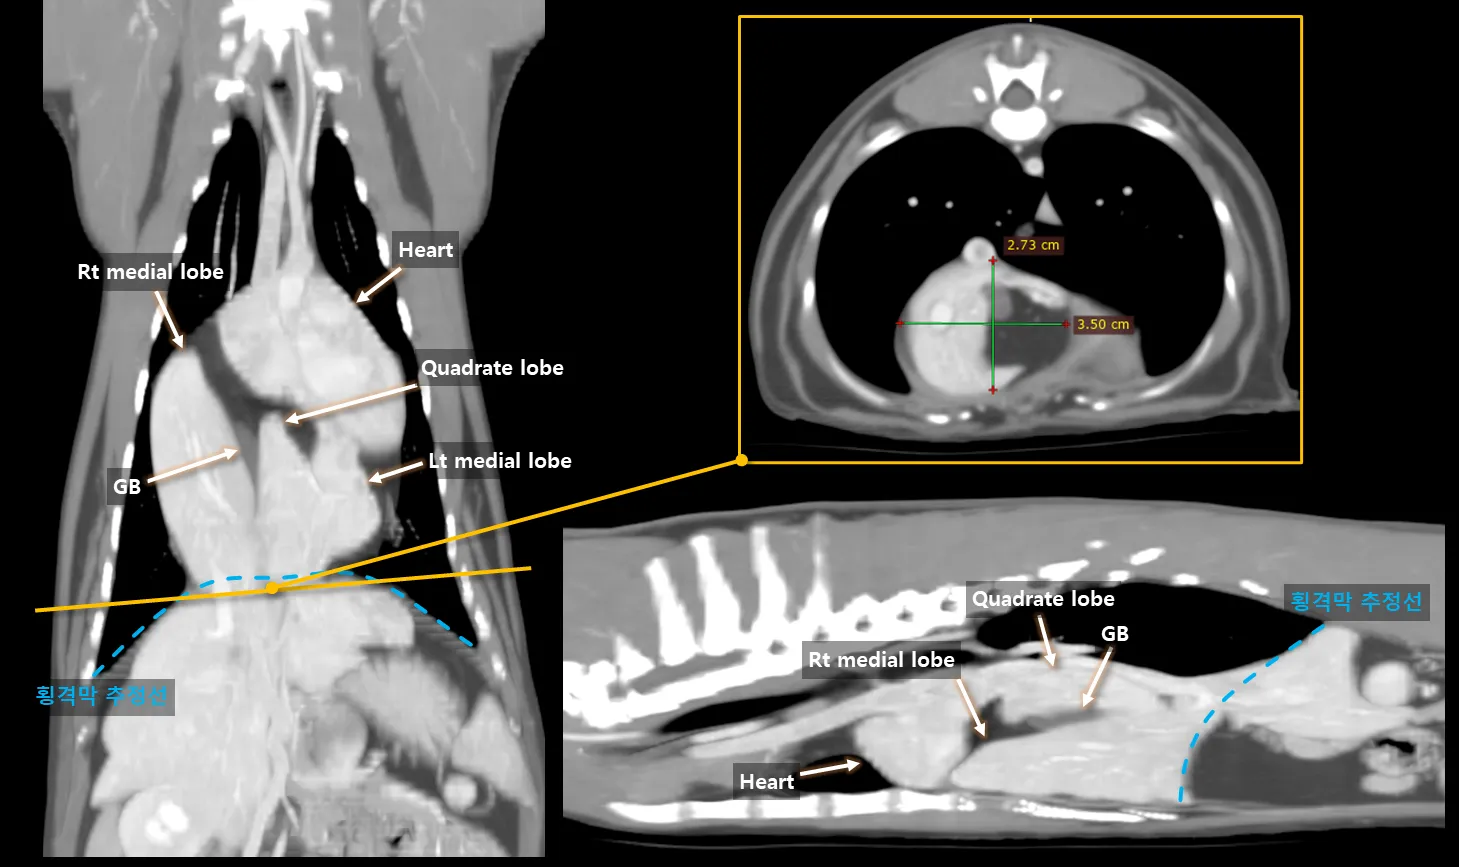

Possibly Gastroduodenal Vein Thrombosis due to Severe Pancreatitis

Summary Signalment λ₯μ€ννΈ, SF, 12y, 6.3kg CC: κ΅¬ν  Conclusion Gastroduodenal vein thrombosis Severe pancreatitis Possibly secondary fat stranding, EHBO and duodenitis Key findings μ·μ₯μ λΆκ·μΉν λ³μ°, μ’

λ, μ λ§₯ μ‘°μμ μΌλΆ μ€μ§μ μ κ°μ (red). μ λ§₯ μ‘°μμ κ°λ¬Έλ§₯ λ° μ-μμ΄μ§μ₯ μ λ§₯μ μ‘°μμ  μΆ©μ§ κ²°μ (yellow). μ·μ₯κ³Ό μΈμ ν λ³΅κ° μ§λ°©μ κ³ κ°μ (yellow) μμ΄μ§μ₯ λ²½ λΉν (mint). μ΄λ΄κ΄μ κ²½λ―Έν νμ₯ (green). μ·μ₯-μμ΄μ§μ₯ λ¦Όνμ  μ’

λ (blue). Additional findings μμΈ‘ λΆμ μ λ¨μΆ μ§κ²½ 6.3mm μμ€μΌλ‘ κ²½λ―Έν μ’

λ (bilaterally symmetric adrenomegaly) Thrombosis & Pancreatitis